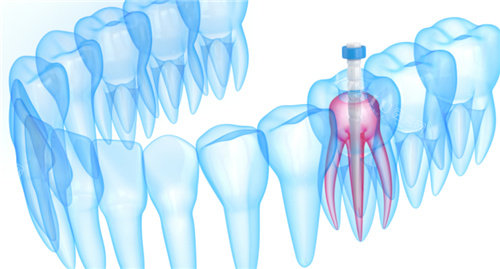

没等一会儿,护士就带我去了诊室。给我看牙的是张医生,他看起来特别和蔼,说话也轻声细语的。张医生先让我躺在牙椅上,然后仔细地检查了我的牙齿,还拍了片子。看着片子,他耐心地跟我说:“你这颗牙因为龋坏太严峻,已经伤到牙髓了,所以才会这么疼。不过别担心,咱们做根管治疗就能把问题解决掉。”接着,他又给我详细讲解了根管治疗的过程,从开髓、拔髓、根管预备到根管填充,每一步都讲得清清楚楚,还回答了我好多问题,让我对根管治疗有了更深入的了解。

张医生开始操作了,他动作特别熟练,每一个步骤都做得很仔细。我能感觉到他在用各种工具清理我的牙髓和根管,虽然能感觉到一些震动,但一点都不疼。治疗过程中,他还时不时地问我有没有不舒服,让我觉得特别安心。整个治疗过程大概持续了一个多小时,虽然时间有点长,但因为有张医生的耐心,我并没有觉得太难熬。